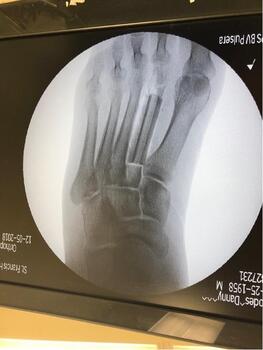

A 61-year-old male suffered multiple gunshot wounds, with one to the abdomen and the other to the left foot. The patient began IV antibiotics, as his injury was a Gustilo Anderson 3a open fracture to the left second metatarsal. We took the patient to the operating room for an emergent left foot incision and drainage with application of external fixation. We noted the second metatarsal shaft was shattered on fluoroscopy and inserted a mini rail external fixation into the preserved metatarsal head and base to preserve length.